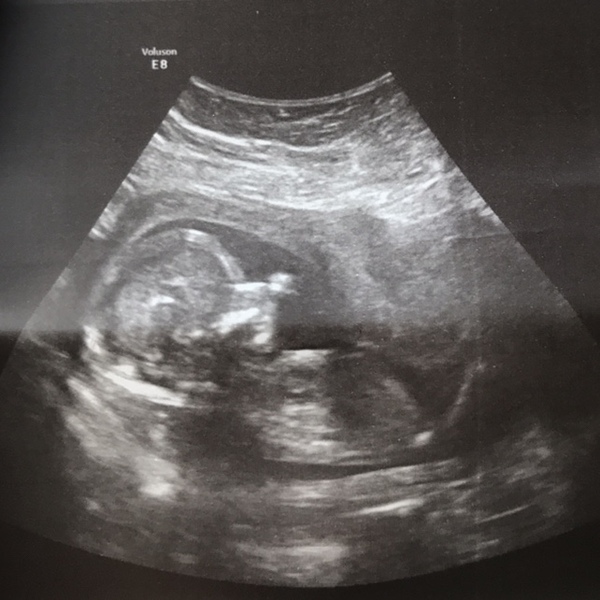

Buk88 · 19/02/2018 12:15

Hello ladies,

Still incredibly sick but the consultant has prescribed new medication so hopefully that will help. Went for a private scan to make sure everything is still ok (I’ve been so worried with being so sick and stressed) and there was peanut waving and chillin’ with his arms behind his head! ❤️ And yes, he’s a he! We’re having a boy!